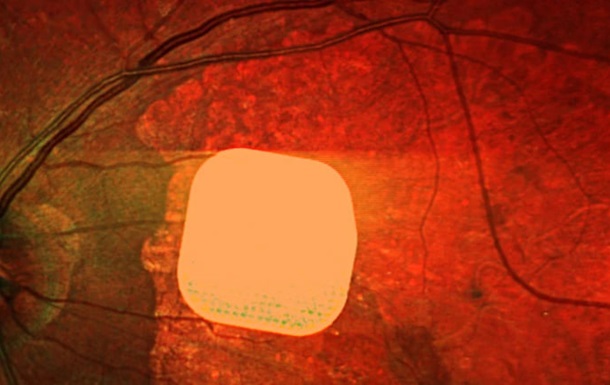

Фото: Science Corporation/PA ультратонкий электронный имплантат

Микрочип размером всего 2×2 миллиметра и толщиной с половину человеческого волоса хирургически устанавливают под сетчатку глаза. Во время операции, которая длится менее двух часов, пациенту также подключают систему очков дополненной реальности с камерой и миникомпьютером. Камера считывает окружающее изображение, преобразует его в инфракрасный сигнал и передает на микрочип, который активирует клетки сетчатки. Затем через зрительный нерв сигнал поступает в мозг, формируя визуальное восприятие.